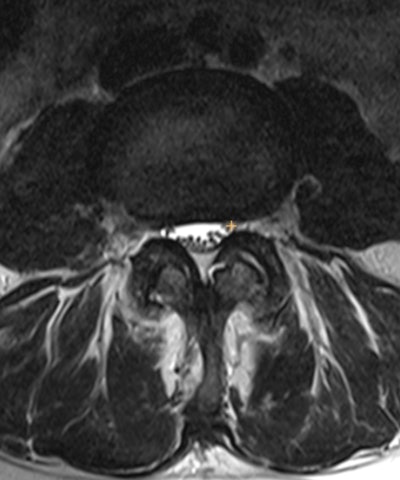

(A, B) MR images (A, sagittal T2; B, sagittal STIR) demonstrate the location of the localizers within the middle of the thecal sac at the level of the L1/L2 through L5/S1. Images and caption courtesy of the RSNA.(A, B) MR images (A, sagittal T2; B, sagittal STIR) demonstrate the location of the localizers within the middle of the thecal sac at the level of the L1/L2 through L5/S1. Images and caption courtesy of the RSNA.

Inclusion criteria consisted of MRI lumbar spine studies with a sagittal "T2-like" (e.g., conventional spin echo T2, STIR, or Dixon), sagittal T1, and axial T2 weighted images. Volunteer annotators graded the degree of stenosis using a four-point scale of normal, mild, moderate, or severe for the following locations: spinal canal (labeled on the T2-like sequence), right and left neural foraminal (sagittal T1), and right and left subarticular recess (axial T2).